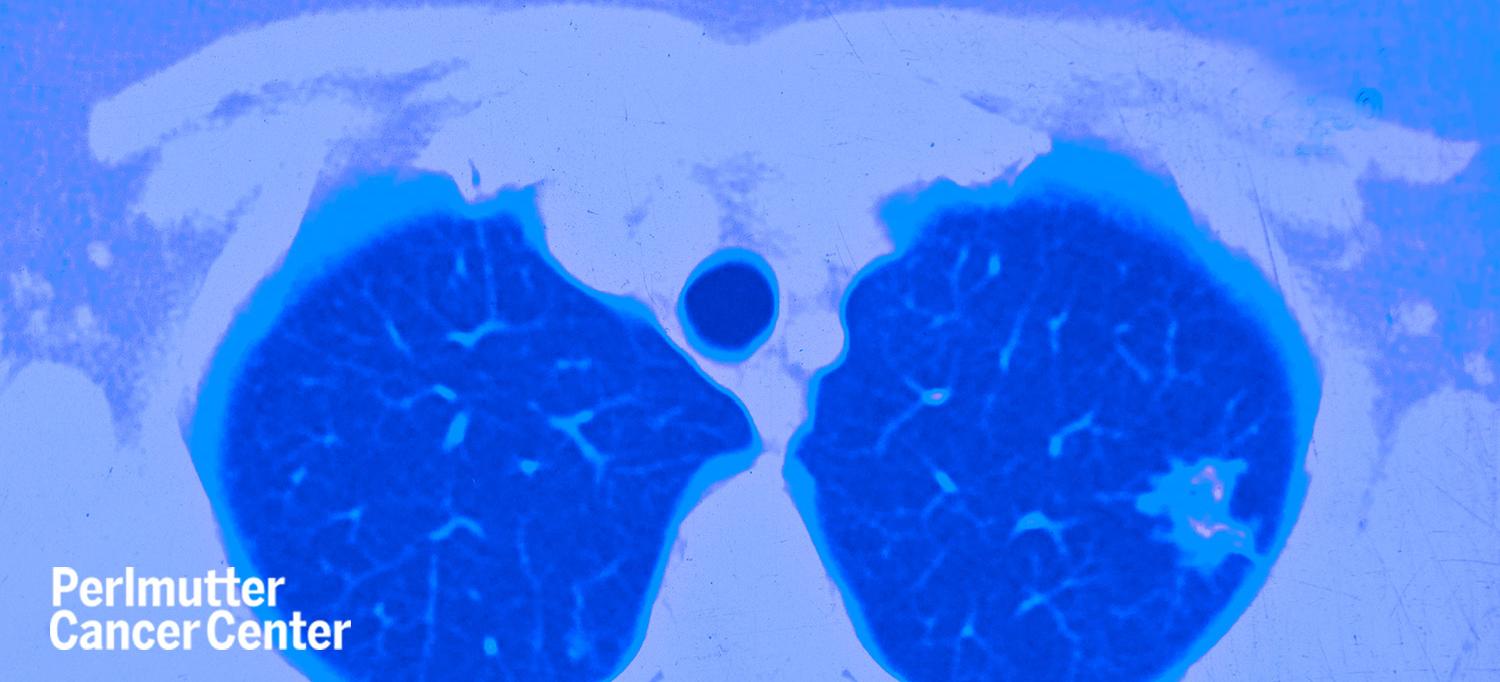

As a respiratory illness, 2019 coronavirus disease (COVID-19) poses a particular risk to people with lung cancer. Joshua K. Sabari, MD, assistant professor in the Department of Medicine and a member of Perlmutter Cancer Center at NYU Langone Health, discusses why people with lung cancer may be at higher risk of developing serious complications from COVID-19, how cancer doctors are reducing their patients’ risk of catching the disease, and more.